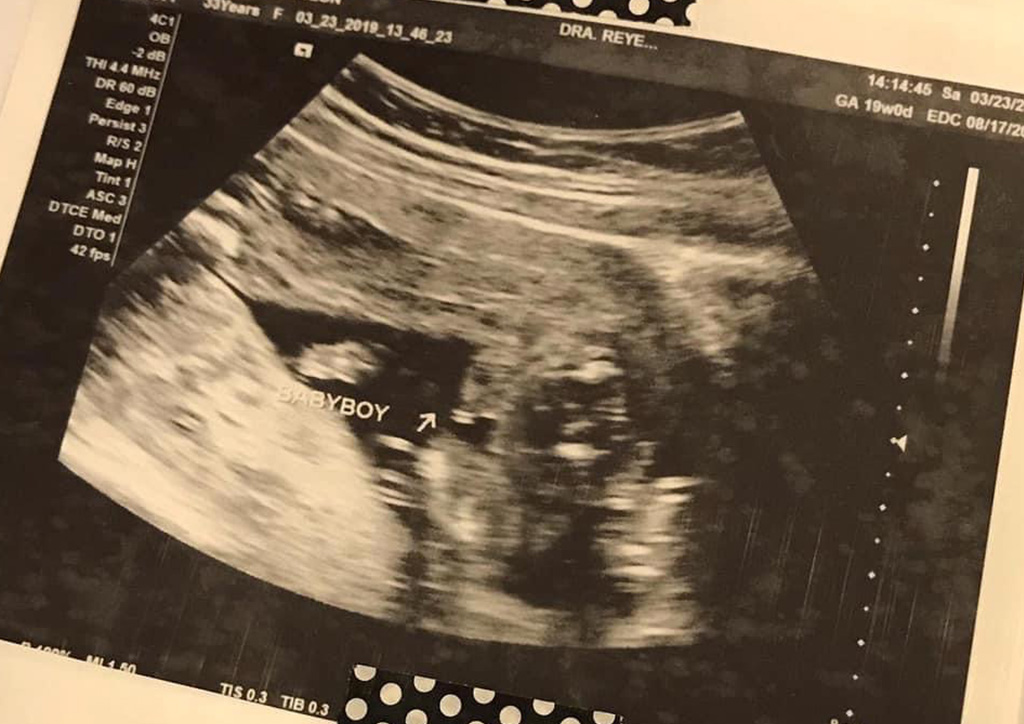

I was 19 weeks pregnant. I was lying there waiting for the sonologist to print my baby’s picture with his/her gender, which I would safely put in a white envelope marked “Do Not Open”. The wait was longer than usual.

“Your baby has pleural effusion, there is water in his lungs, he also has a congenital heart disease called AVSD, it’s Atrioventricular Septal Defect which basically means he has a big hole in the middle of his heart”.

She then showed me the screen but all I saw was a blurry sea of black and white. She proceeded in telling me that she also found several more defects. Around this time, I was already in tears but I was trying hard to listen to what she was telling me so I could remember everything when I had to tell my husband.

Then, she goes, “Your baby may have down syndrome based on our findings. But let’s do a confirmatory test after you see your OB.”

And this is how I found out about Rocco’s condition, at 19 weeks of pregnancy. Some moms only discover about their baby’s condition upon giving birth, while others, like in my case, are detected early through congenital anomaly scan or even just the regular pelvic ultrasound.